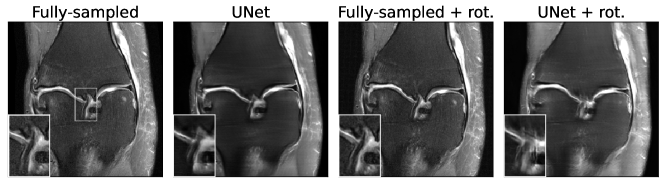

The SSIM scores after adversarially attacking our models with rotations are shown in Fig. 4. Comparing Fig. 4(a) with Fig. 1(a) above, it can be seen that rotation attacks are less severe than attacks with adversarial noise which is not unexpected given the much higher degree of freedom of the noise attacks. However, the rotation attacks, although very small and purportedly benign in nature, can still manage to substantially degrade the output of the algorithm. From Fig. 4(b) it can be observed that the attack is continuous in θ𝜃\theta and a non-negligible range of rotation angles leads to substantial drops in SSIM. This indicates that such degradation could realistically occur in clinical practice. A qualitative example of a UNet reconstruction is shown in Fig. 5. While the rotation has negligible effects on the fully-sampled reconstruction (third column), it can be seen that the UNet attacked with the same rotation (fourth column) produces an image where the ACL appears fuzzy (similar to the example in Fig. 3). As in the previous examples, this could potentially lead to a misdiagnosis.

Refer to caption

Figure 5: Effects of small rotation on the reconstruction quality (8×\times acceleration). For the worst-case angle of -4.9°, the annotated region gets more fuzzy, potentially leading to a misdiagnosis of an ACL tear instead of a low grade sprain.